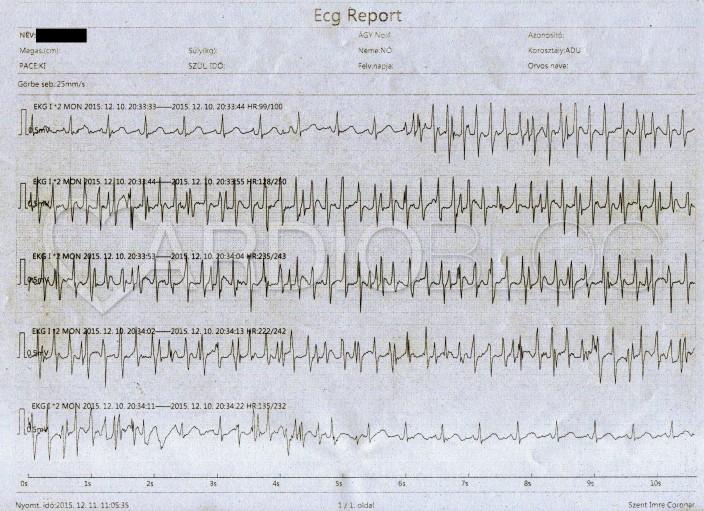

Egy fiatal nőbeteget anticoncipiens hatás miatt kialakult nagy kiterjedésű tüdőembólia okán observaltunk coronaria őrzőnkben. Egyik esti fogmosásakor hirtelen ezt észleltük:

Mi látható az EKG-n? Mit tegyünk? Mit tanácsoljunk a nőbetegnek?

Fogmosás okozta műtermék

Ha egy ritmuszavar kezdete vagy vége látható az EKG-n sokkal könnyebb dolgunk van, mert össze tudjuk vetni az alapritmussal. Ha most kellő figyelmességgel felmértük az alap sinus ritmus reguláris R-hullámait az első pillantásra ijesztőnek tűnő jelenségre, akkor észrevehettük, hogy teljes változatlansággal minden folytatódik ugyanúgy, mint addig.

Sem supraventricularis, sem kamrai ingerképzés nem tud azonban olyat létrehozni, hogy az ábrán látható rövid kapcsolási idővel a szívizomzat újra excitálódjon:

A képet mozgási műtermék okozza, a fogmosás eredményezi. A monitor által ~250/perces frekvencia a szubmasszív tüdőembóliában a keringés összeomlását eredményezte volna, így a beteg a fogmosást nem tudta volna folytatni.